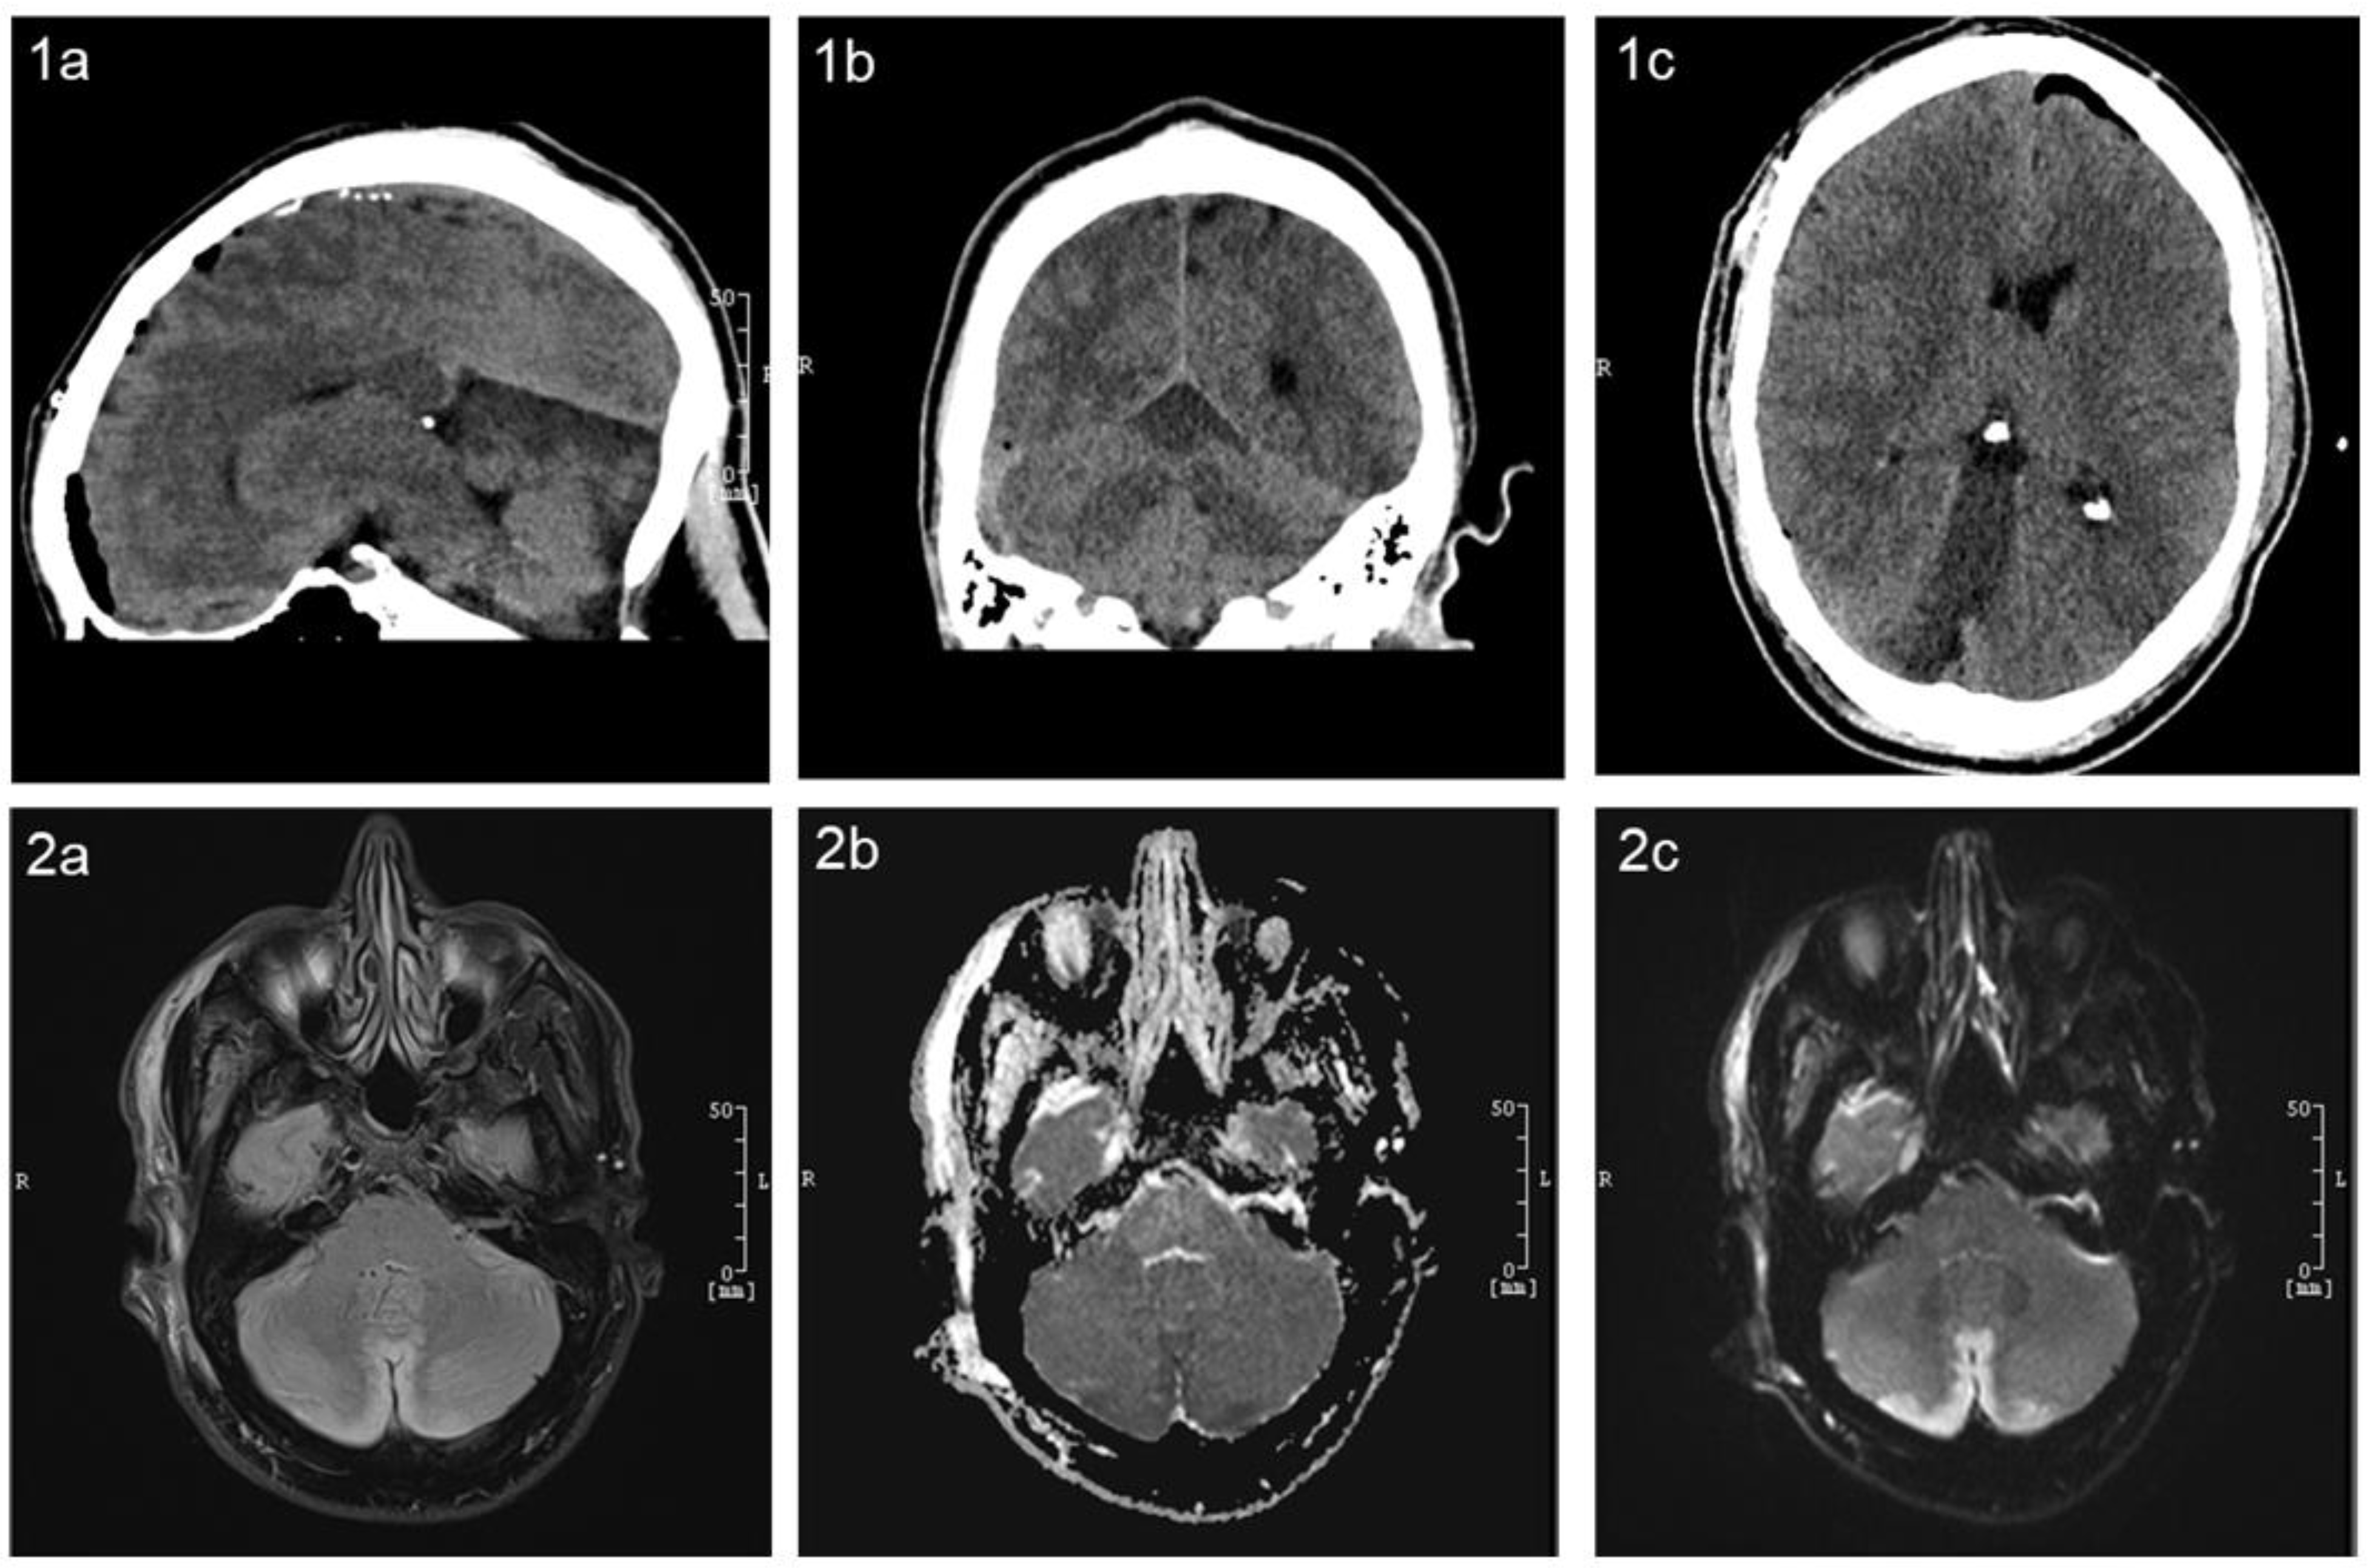

Postoperatively, anisocoria (right pupil larger than the left) was observed in the operating room, raising immediate concern. A prompt CT scan was performed, revealing no acute abnormalities and providing initial reassurance. Further investigation with CT perfusion and angiography showed no evidence of vasospasm or perfusion deficits. The clinical course took a significant turn a few hours later when the patient suffered a generalized tonic–clonic seizure, necessitating re-intubation in our neurosurgical ICU. Repeat imaging, conducted 3 hours after the initial CT, revealed a diffuse infarction, most likely located in the territory of the superior cerebellar artery (SCA), without clear territorial demarcation (Figure 3). The patient’s medical history and family reports suggested potential amphetamine use on the day before surgery, possibly even immediately before the procedure. A drug screening confirmed the presence of amphetamines, aligning with the family’s account. Amphetamines are known to remain detectable in urine for up to 3–4 days after consumption. Subsequent MRI imaging confirmed a cerebellar infarction bilaterally in the paramedial region, involving the vermis and the superior cerebellar artery’s supply area (Figure 3). The TOF sequence showed no evidence of occlusion in the major brain-supplying vessels.

Figure 3. Non-contrast CT and MRI of the brain showing a hypodense area in the superior cerebellum, consistent with an infarction in the territory of the superior cerebellar artery (SCA). This finding correlates with the patient’s perioperative neurological symptoms. Panels (1ac) show the postoperative CT scan in sagittal, coronal, and axial views. Panel (2a) displays the postoperative brain MRI in T2-FLAIR sequences, while panel (2b) presents diffusion-weighted imaging with apparent diffusion coefficient mapping sequences and (2c) present standard diffusion-weighted imaging sequences.